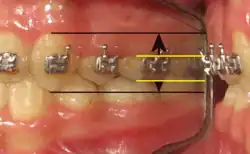

- Au cours de cette permutation dentaire (enfant, adolescent), toute augmentation artificielle temporaire de la hauteur clinique des dents permute le mouvement horizontal originel de la langue (déglutition infantile) en une transposition verticale (crâniale), accompagnée de pressions centrifuges sur la voûte palatine et ses parois osseuses (os alvéolaire). L'élévation linguale de la déglutition salivaire physiologique est provoquée par une adjonction iatrogène de résine composite, ou « plombage blanc », matériau collé sur les faces occlusales (triturantes) de deux molaires, lactéales ou permanentes. C'est le principe des réducteurs d'espace interocclusal de repos, ou REIOR (1999).

- Direction du travail lingual et REIORs :

- La direction horizontale du travail lingual (déglutition infantile, déglutition atypique) devient verticale (déglutition physiologique) par l'adjonction de deux REIORs, de 3 à 6 millimètres d'épaisseur, sur les faces occlusales de deux molaires, gauche et droite, lactéales ou permanentes. Modifier la direction du travail lingual supprime tout zézaiement et chuintement, rend les lèvres plus lipues et réduit agréablement le double menton. Quel que soit l'âge du patient, la présence des REIORs ne contrarient nullement la mastication, ni l’imprégnation salivaire des aliments.

- Dans le cas de plusieurs REIORs posés entre avril 2005 et décembre 2010 chez une adolescente (DN 06/07/1994), on constate :

- 1. Une faible augmentation antéro-postérieure du segment « A - B » (5,88 %) ;

- 2. Une diminution de l'angle formé par la face vestibulaire de l'incisive centrale et le plan frontal ;

- 3. Une diminution notable du diastème inter incisif, ou « signe de richesse » ;

- 4. La permutation des canines (10 ans) entraîne une augmentation significative de la distance inter canines et une mésialisation des cuspides canines, ou [(E - F) x 2] ;

- 5. Le déplacement peu significatif (5,88 %) de la cuspide linguale de la première prémolaire ;

- 6. Une augmentation significative de la distance inter molaires [(C - D) x 2] de 74 pixels dans le plan frontal : c'est le témoin de l'expansion transversale des tissus osseux (palais, sinus maxillaires et fosses nasales) et le patient témoigne d'une facilitation de la respiration nasale ;

- 7. Sous la distance « A - B » constante et « C » pris comme point de référence géométrique (2005), l'augmentation de la surface palatine correspond au couloir compris entre les deux lignes bleues superposées sur le cliché du 13-04-2005.